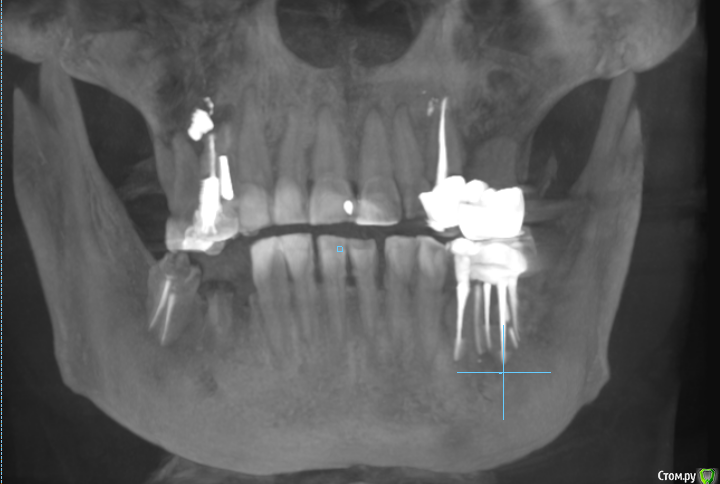

msa Опубликовано 27 февраля, 2019 Поделиться Опубликовано 27 февраля, 2019 Здравствуйте, уважаемые доктора!Прошу совета в выборе оптимального плана лечения и восстановления зубного ряда.Слева вверху (2.3-2.6) мост м/к с 1998 г(со слезами обточила здоровый красивый клык).Справа внизу был мост м/к 2006г на 4.4-4.7 (опорный моляр 4.7 + штифт в 4.5, конструкция была не очень, т.к. не отдала обтачивать под коронку клык 4.3) Через 7 лет мост слетел… От слова совсем.В н/вр пытаюсь понять, нужно ли бороться за премоляр 3.5 Или однозначно удалять? Можно ли сохранить 3.6 с помощью культевой вкладки?Какие варианты оптимального замещения низа справа 4.4-4.7? Корни пока не удаляю. Жизнеспособен ли верх 1.4-1.6? (пломбам больше 20 лет) Скриншоты из КТ от 25.02.19 ОПТГ не делалаСпасибо!С уважением, Марина Ссылка на комментарий

suballex Опубликовано 4 марта, 2019 Поделиться Опубликовано 4 марта, 2019 Ревизия 14,15 терапевтом.Ревизия 37,36,35,34 терапевтом. По результатам ревизии - решение о сохранении зубов. Не по результатам КТ. Врачи лечат не рентген, а пациента. Терапевт убирает все реставрации и рецидивы, оценивает объем сохраненных тканей.47,45 удалитьИмпланты 46,44Если после ревизии все зубы сохраняются:- Коронки на свои зубы 14,15,37,36,35,34- Мостовидный протез на импланты 46-44 23,26 предоставленной информации не достаточно. А ссылка ваша глючит. 1 Ссылка на комментарий

msa Опубликовано 4 марта, 2019 Автор Поделиться Опубликовано 4 марта, 2019 suballex, Saymon, спасибо Вам большое, что откликнулись. С вашей помощью уже пишу план лечения.Ортопед клиники, где я все время лечила зубы, отказала мне в лечении вкладкой или коронкой 35 зуба(разрушена коронка значительно). Предложила вариант сохранить зуб пломбой, если согласится лечащий врач. Проблему у 36 она даже и не увидела внешне. После этого я сделала КТ, насмотрелась на снимки, проконсультировалась в др. клинике и до меня дошел масштаб бедствия...Кстати, после посещения клиники, где мне предложили сразу все удалить по КТ, лечиться там уже не хочу. suballex, ссылку я обновилаhttps://drive.google.com/file/d/1csTSnoHz4mgWTkieKcR-4hOGVxjxPYFp/view?usp=sharingЕще раз спасибо Вам за помощь.С уважением, Марина Ссылка на комментарий